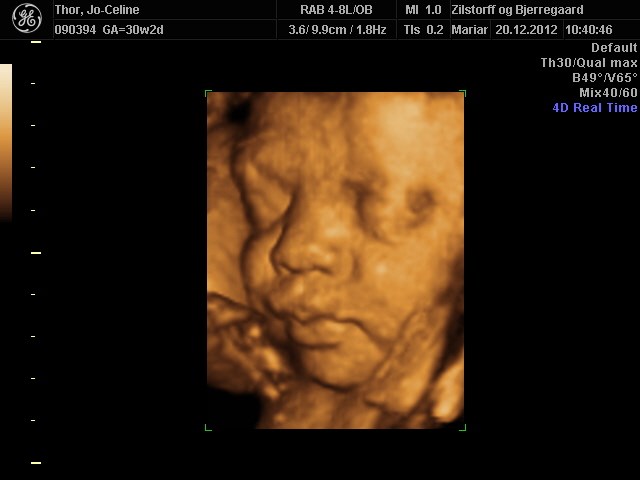

Søger man på Google kommer der kun 3D-billeder.

Så jeg vil høre om nogen herinde har et billede eller to fra uge 28 de vil vise? Og hvor lang var jeres baby, og fik I vægt at vide?